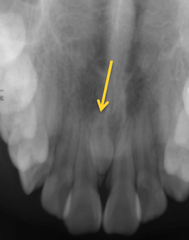

Depression on the mandible at the inferior alveolar canal- submandibular gland a)Ranula b)Pleomorphic adenoma c)epidemic parotitis (mumps) d)Stafne's bone cyst

Front

Stafne's bone cyst

Back